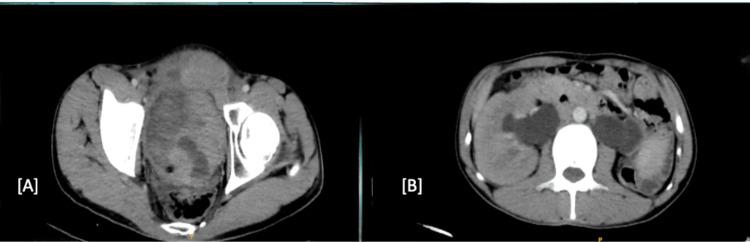

Sarcomatoid urothelial carcinoma (SUC) is a rare and aggressive variant of urinary bladder cancer and is associated with a poor prognosis. This case report presents the unusual case of a 29-year-old male who presented with a vesicocutaneous fistula causing continuous suprapubic urine leakage for four months following a previous bladder surgery for a vesical calculus. This patient had no history of hematuria, which is a common symptom of bladder cancer. Investigations, including contrast-enhanced computed tomography (CECT) and 18F-fluorodeoxyglucose (FDG) positron emission tomography-computed tomography (PET-CT), revealed a large, locally advanced bladder mass infiltrating the anterior abdominal wall with a vesicocutaneous fistula. The patient underwent a radical cystoprostatectomy, wide local excision of the fistulous tract, bilateral pelvic lymph node dissection, right cutaneous ureterostomy, and abdominal wall reconstruction with a pedicled anterolateral thigh flap. Histopathology confirmed poorly differentiated SUC. This case is unique due to the patient's young age, the atypical presentation with a vesicocutaneous fistula without hematuria, and the sarcomatoid histology. It highlights the aggressive nature of SUC, its potential for unusual presentations that can delay diagnosis, and the necessity of considering bladder cancer in young patients with urinary fistulas, even without hematuria. Radical surgery with meticulous reconstruction offers the best chance for disease control in such complex scenarios, emphasizing the importance of early suspicion and multidisciplinary management.

肉瘤样尿路上皮癌(SUC)是膀胱癌一种罕见且侵袭性强的变异类型,预后较差。本病例报告呈现了一名29岁男性的不寻常病例,该患者在先前因膀胱结石进行膀胱手术后出现膀胱皮肤瘘,导致耻骨上持续漏尿四个月。该患者无血尿病史,而血尿是膀胱癌的常见症状。包括增强计算机断层扫描(CECT)和18F-氟脱氧葡萄糖(FDG)正电子发射断层扫描-计算机断层扫描(PET-CT)在内的检查显示,有一个巨大的、局部进展性膀胱肿块,侵犯前腹壁并伴有膀胱皮肤瘘。患者接受了根治性膀胱前列腺切除术、瘘管广泛局部切除术、双侧盆腔淋巴结清扫术、右侧皮肤输尿管造口术以及带蒂股前外侧皮瓣腹壁重建术。组织病理学证实为低分化SUC。该病例独特之处在于患者年轻、无血尿的膀胱皮肤瘘非典型表现以及肉瘤样组织学特征。它突出了SUC的侵袭性本质、其可能出现延迟诊断的不寻常表现,以及在即使无血尿的年轻尿瘘患者中考虑膀胱癌的必要性。在这种复杂情况下,精心重建的根治性手术为疾病控制提供了最佳机会,强调了早期怀疑和多学科管理的重要性。